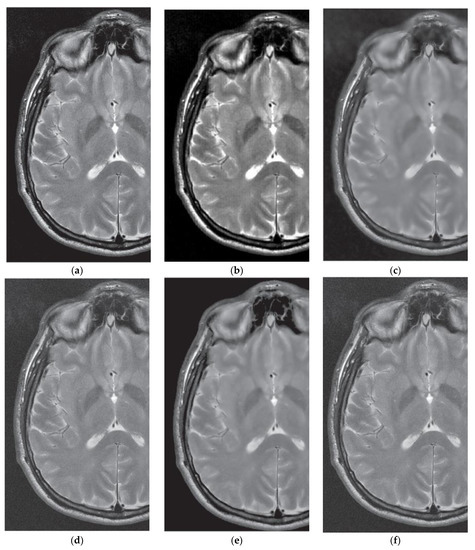

3.4. Comparative Performance in Real MRI